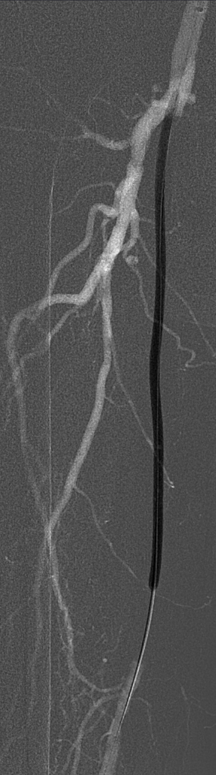

标准化操作流程(Tips)

开通:以内膜下技术为主,逆穿是常用且有效的辅助手段。

预扩:充分预扩张至关重要,需逐级使用高压球囊,最终达到 6mm 直径,以获得足够的管腔。

支架植入:遵循“由远及近”原则,先放置远端 DES,再覆盖中段 VB,最后处理近端。利用 Eluvia 的可调节性优化重叠。

后扩:常规使用 6mm 高压球囊进行后扩张,确保支架充分贴壁和管腔获得。

用药:术中术后必须充分抗凝,推荐“双通道”抗栓方案(如利伐沙班+阿司匹林),以模拟 bypass 的血流动力学效果。